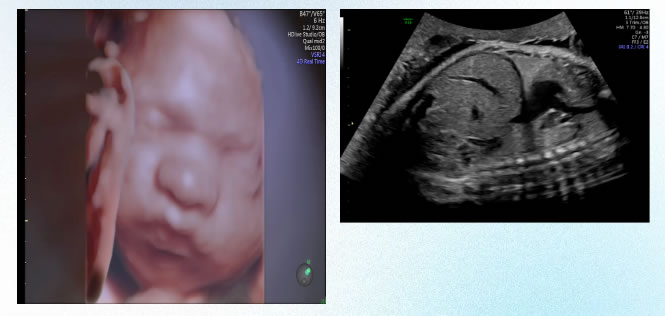

未命名-2.jpg

第一次超聲產前篩(shāi)查(chá):孕11-13+6周,NT篩查,預測胎兒(ér)患染色(sè)體異常的風險,以及對胎兒結構進行係統(tǒng)的(de)早(zǎo)期篩查(chá)。

未命(mìng)名-12.jpg

第二次超(chāo)聲產前篩查:孕20-24周,係統超聲檢查(產前III級超聲檢查(chá)),也稱大排畸超聲,主要對胎兒各個(gè)解剖(pōu)結構及係統進行全麵的結構篩查;主要篩查九大致死性胎兒畸形。